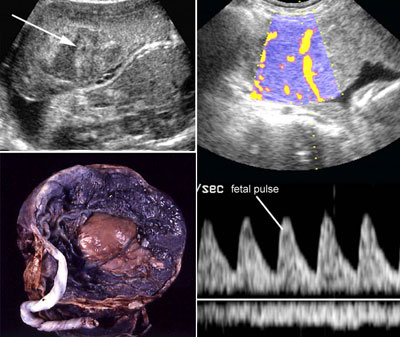

Abruptio placentae

Click the image to magnify it

Legend:Abruptio placentae